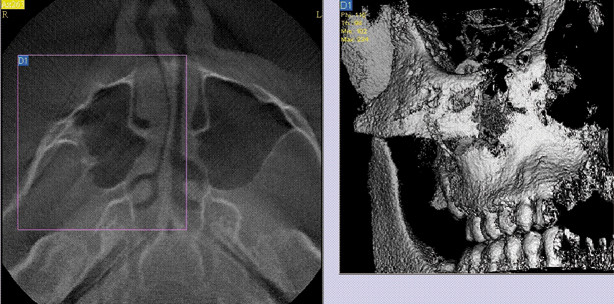

Entdeckung und Beurteilung von ­Knochenbrüchen

Im Bereich der Gesichts- und Kieferknochen sind Knochen­brüche oft besonders schwierig zu diagnostizieren. Feine Fraktur­linien, kleine Knochenfragmente und vor allem Überlagerungen verschiedener Strukturen komplizieren die Entdeckung und Beurteilung der Situation. Zum Beispiel in der Nähe des Kiefergelenks ist die Einschät­zung ebenso diffizil wie folgenreich, denn hier können kleine Brüche mitunter große Folgeprobleme nach sich ziehen. Die Frage nach der besten Therapieoption, der Verant­wort­barkeit eines konservativen Vorgehens oder die Notwendig­keit einer Operation sollte aber im optimalen Fall zügig geklärt werden ­können. Auch die feinen Veränderungen im Behand­lungs­verlauf müssen beurteilt werden, heilt die Fraktur oder verschieben sich die Fragmente weiter, wächst gar der Fraktur­spalt. Das DVT zeigt selbst kleine Knochen­verschie­bungen bei feinen Knochenbrüchen (Abb. 9a und b). Auch die Möglichkeit der Dokumentation ist für den einzelnen Patienten oft sehr wichtig. Kann man zum Beispiel nach einem Berufsunfall oder Schulunfall die Nasenbeinfraktur mit Bildern belegen, so hat der Patient bei Spätveränderungen etwas in der Hand, um den BG-Fall zu beweisen und die Kostenübernahme zu erreichen, auch wenn direkt nach der Verletzung primär gar keine Opera­tions­indikation gegeben war.